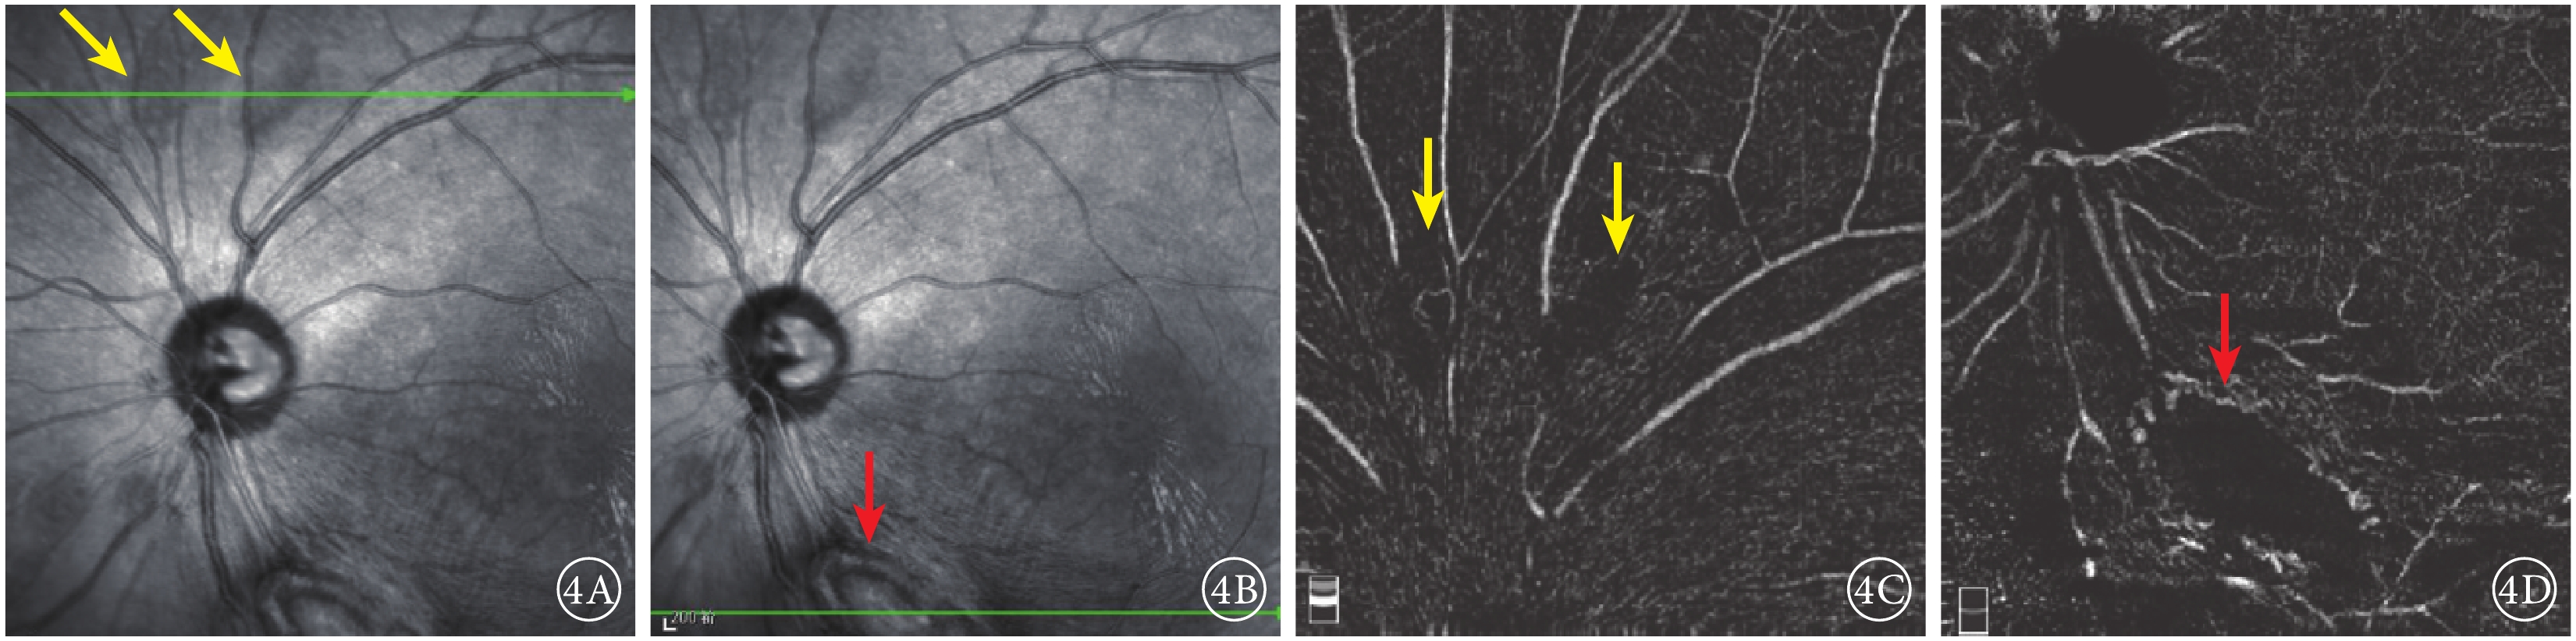

圖4

患者左眼IR及OCTA像。 4A.IR像,視盤上方可見兩處類橢圓形病灶(黃箭);4B.IR像,視盤下方大病灶隆起,結構紊亂(紅箭);4C.OCTA像,與圖4A對應病灶處未見明顯異常;4D.OCTA像,與圖4B對應病灶處周邊部分可見血流信號(紅箭)

圖4

患者左眼IR及OCTA像。 4A.IR像,視盤上方可見兩處類橢圓形病灶(黃箭);4B.IR像,視盤下方大病灶隆起,結構紊亂(紅箭);4C.OCTA像,與圖4A對應病灶處未見明顯異常;4D.OCTA像,與圖4B對應病灶處周邊部分可見血流信號(紅箭)

紅外眼底成像(IR)檢查,左眼視盤下方隆起病灶,結構紊亂,視盤上方可見兩處類橢圓形病灶(圖4A,4B)。光相干斷層掃描(OCT)血管成像(OCTA)檢查,左眼視盤下方病灶周邊部分可見血流,其余小病灶未見明顯異常(圖4,4D)。結合病史及輔助檢查,診斷為結節性硬化并發視網膜星形細胞錯構瘤。OCT檢查,左眼視盤下方視網膜光帶呈圓頂狀隆起,光帶增寬且反射增強,病灶內呈蟲蝕狀,各層結構不清,周圍視網膜層間水腫伴神經上皮脫離,其余各病灶對應區域OCT斷面上視網膜內層光帶增厚隆起,反射增強(圖5)。

圖4

患者左眼IR及OCTA像。 4A.IR像,視盤上方可見兩處類橢圓形病灶(黃箭);4B.IR像,視盤下方大病灶隆起,結構紊亂(紅箭);4C.OCTA像,與圖4A對應病灶處未見明顯異常;4D.OCTA像,與圖4B對應病灶處周邊部分可見血流信號(紅箭)

圖4

患者左眼IR及OCTA像。 4A.IR像,視盤上方可見兩處類橢圓形病灶(黃箭);4B.IR像,視盤下方大病灶隆起,結構紊亂(紅箭);4C.OCTA像,與圖4A對應病灶處未見明顯異常;4D.OCTA像,與圖4B對應病灶處周邊部分可見血流信號(紅箭)

紅外眼底成像(IR)檢查,左眼視盤下方隆起病灶,結構紊亂,視盤上方可見兩處類橢圓形病灶(圖4A,4B)。光相干斷層掃描(OCT)血管成像(OCTA)檢查,左眼視盤下方病灶周邊部分可見血流,其余小病灶未見明顯異常(圖4,4D)。結合病史及輔助檢查,診斷為結節性硬化并發視網膜星形細胞錯構瘤。OCT檢查,左眼視盤下方視網膜光帶呈圓頂狀隆起,光帶增寬且反射增強,病灶內呈蟲蝕狀,各層結構不清,周圍視網膜層間水腫伴神經上皮脫離,其余各病灶對應區域OCT斷面上視網膜內層光帶增厚隆起,反射增強(圖5)。